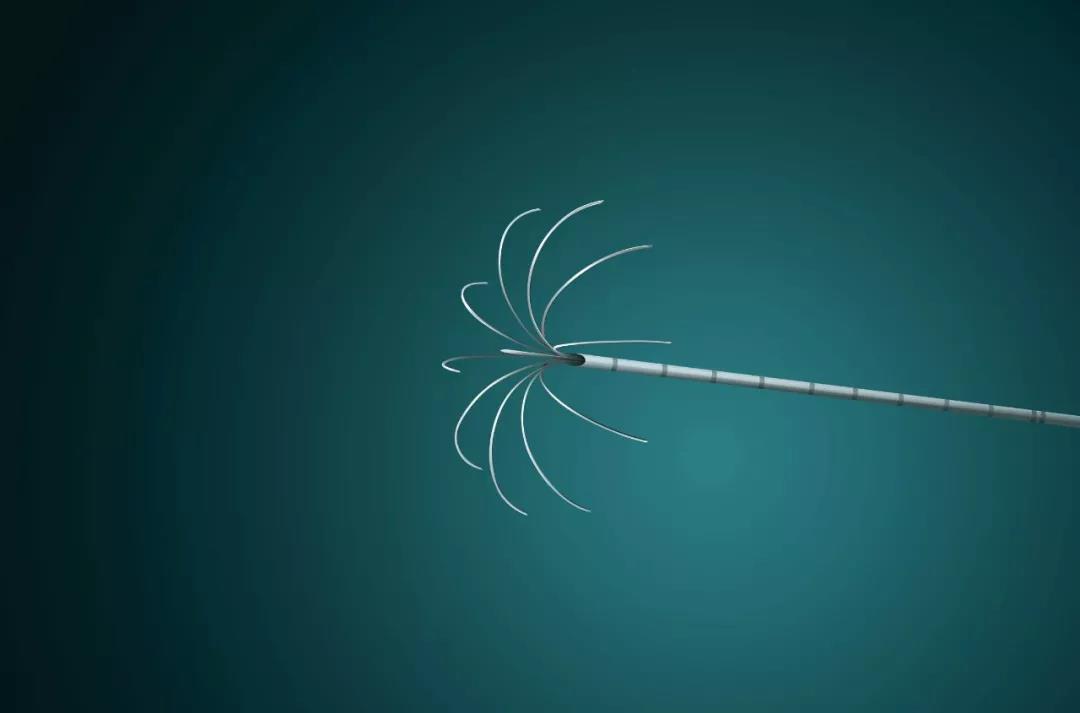

幸运的是,第一个阶段的手术非常成功,张宇华和团队通过5个5-10mm的小孔,把患者病变侧的门静脉右支进行结扎,然后通过离断左右半肝间的肝实质来分隔两侧肝脏。术后,高大伯没有出现任何并发症,第一次手术后3天就出院啦。

“传统的二步肝手术创伤大,并发症多,很多病人因此止步于第一步。腹腔镜技术应用于ALPPS,两步手术都通过微创来完成,明显减少了患者的创伤,在第一步手术中,胆漏、出血等并发症发生率特别低,从而保证了第二阶段手术的顺利进行。”